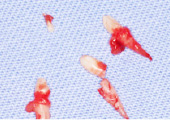

歯肉、歯根膜、歯槽骨骨膜などから発生し、歯肉に限局した良性の腫瘤で、炎症性・反応性の増殖物のことです。